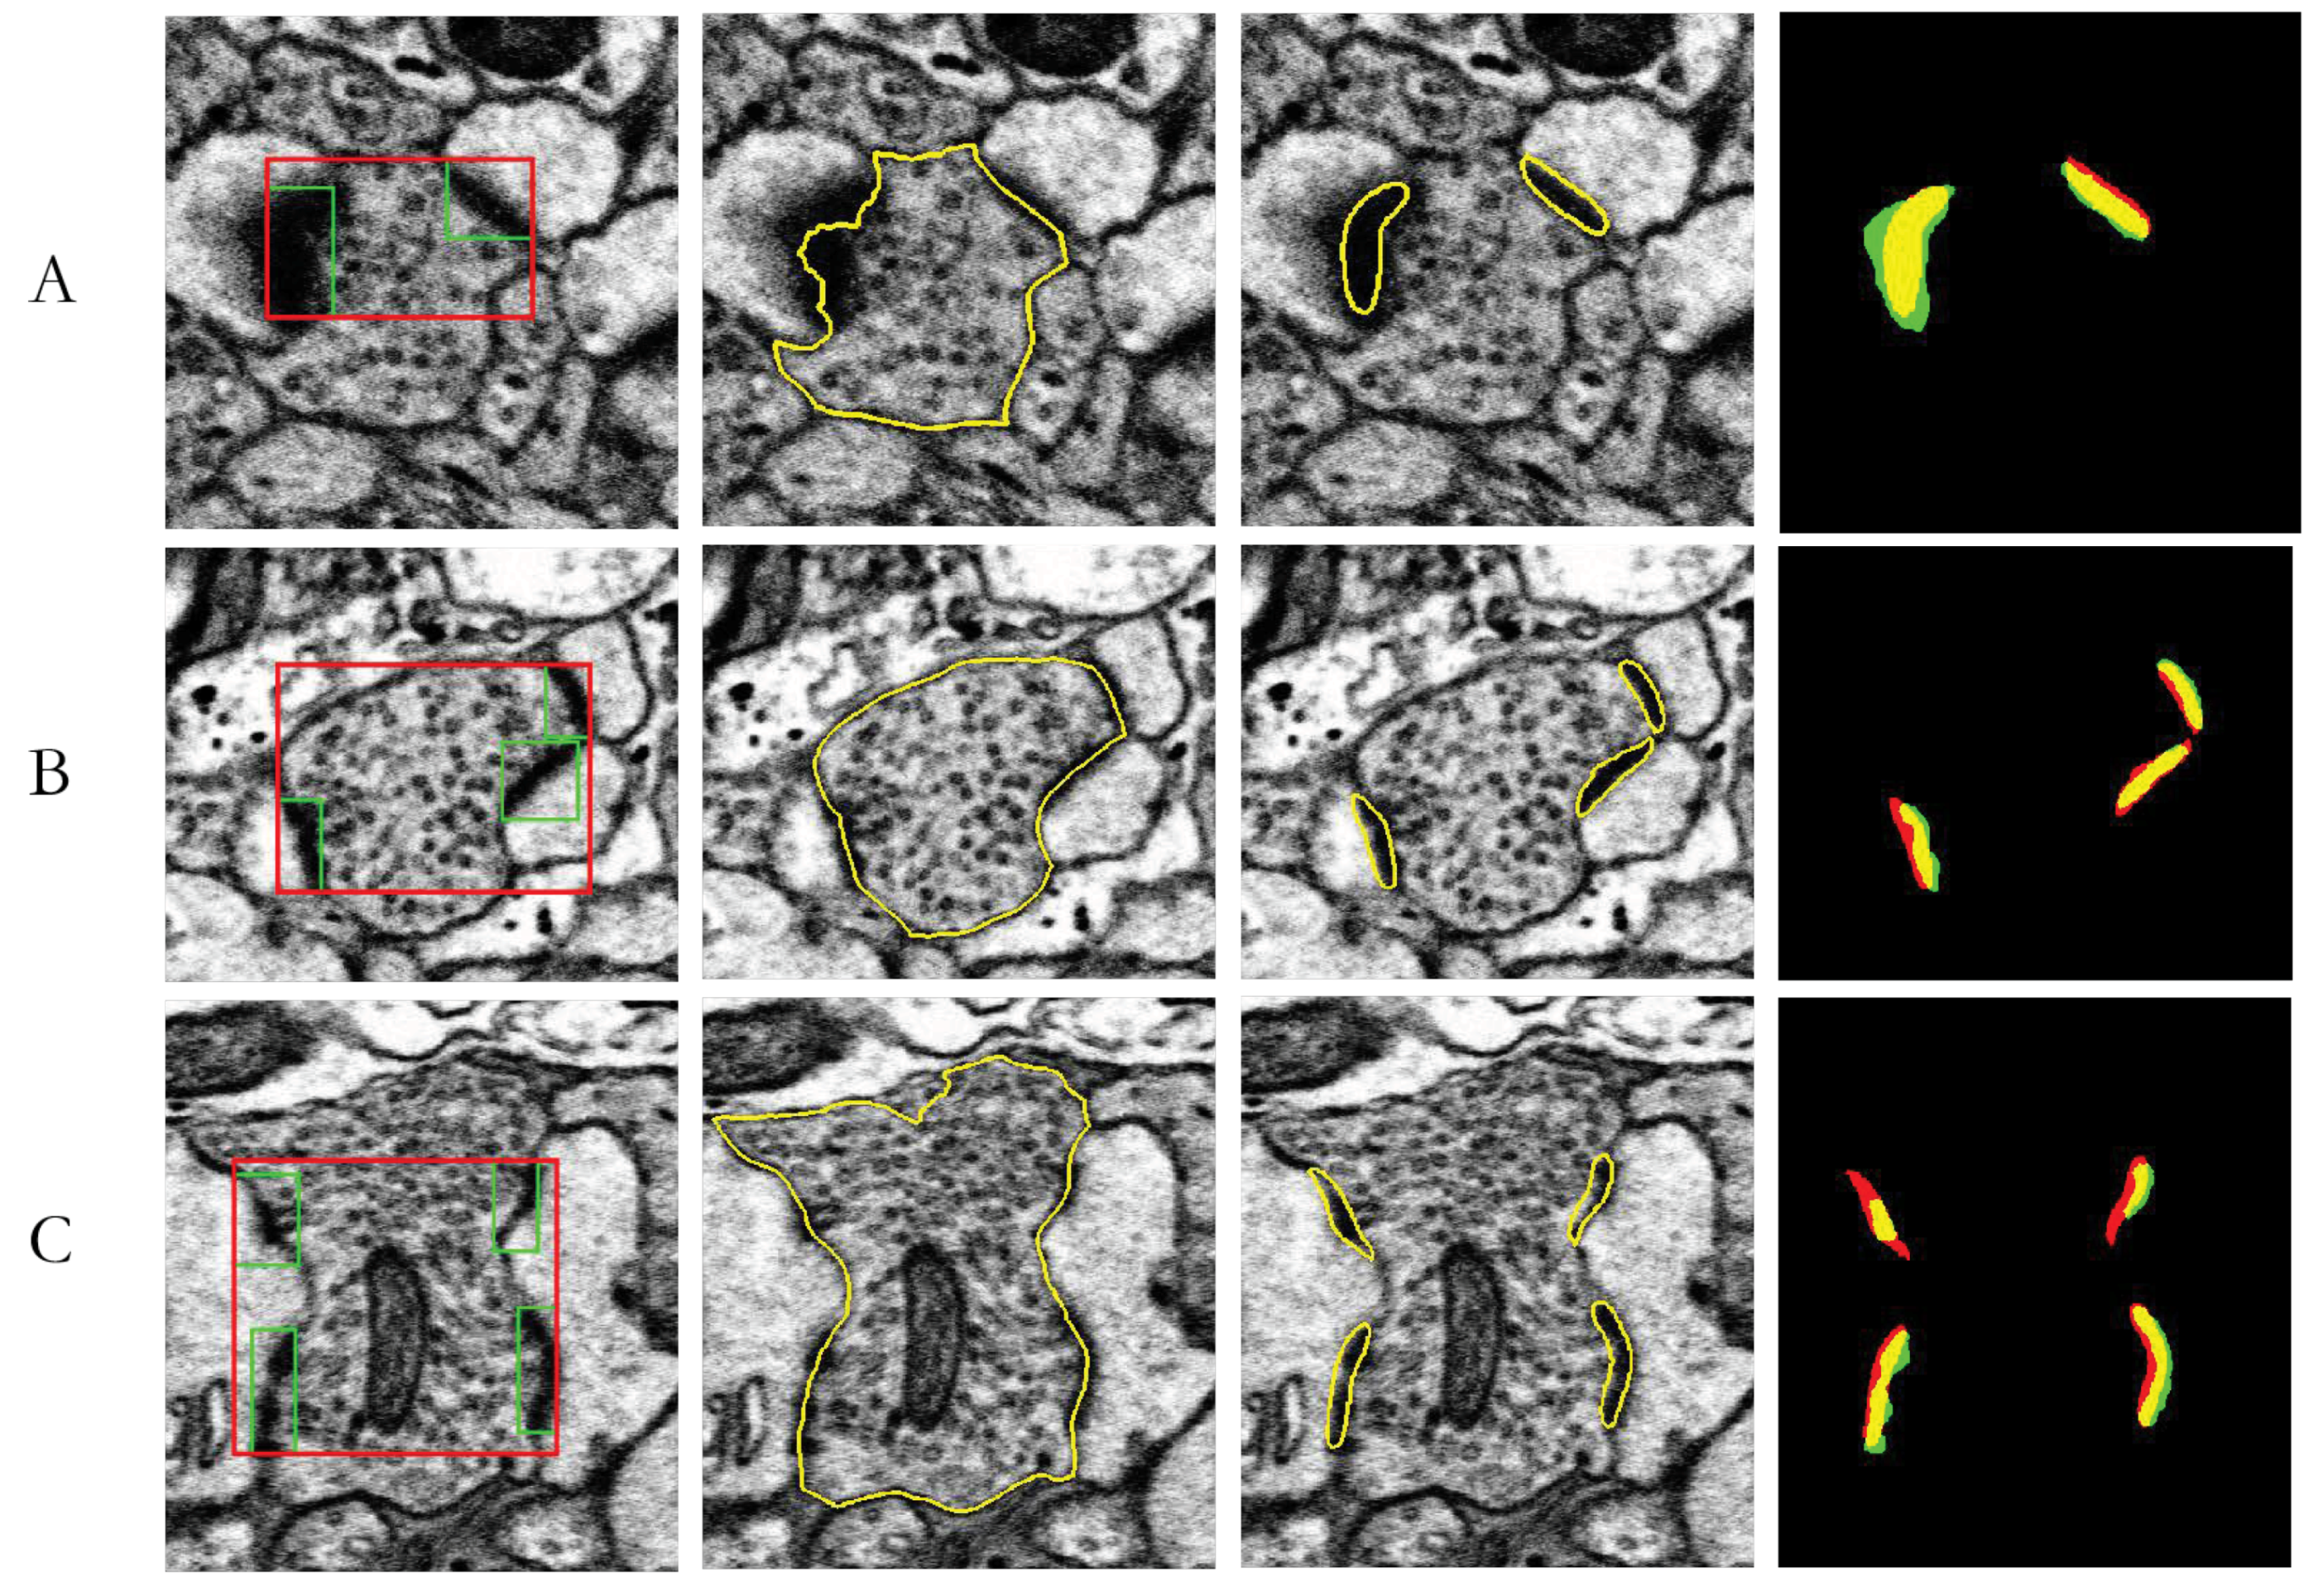

| J(Synapses, Ground truth) | Area(Neuron) (µm2) | Area(Synapse) (µm2) | Area(Neuron)/Area(Synapses) | |

|---|---|---|---|---|

| A | 62.54% | 0.2050 | 0.0266 | 12.98% |

| B | 57.48% | 0.3634 | 0.0334 | 9.20% |

| C | 48.40% | 0.6497 | 0.0048 | 7.40% |